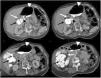

Una mujer de 80 años de edad con antecedente de hipertensión arterial sistémica y apendicectomía abierta a los 35 años de edad, acude al servicio de urgencias por un cuadro de 24h de evolución caracterizado por dolor abdominal progresivo localizado en mesogastrio de tipo cólico con irradiación hacia la región dorsolumbar derecha, sin otra sintomatología asociada y sin datos clínicos que sugirieran obstrucción intestinal. En la exploración física, no presenta alteración en los signos vitales; en la región abdominal se identificó una tumoración blanda en epigastrio, ruidos peristálticos disminuidos, dolor a la palpación en hemiabdomen derecho y ausencia de datos de irritación peritoneal. En sus estudios de laboratorio resaltaba: una hemoglobina en 11.1g/dl, leucocitos en 16.2×103/mm3, neutrófilos en el 91.7% y linfocitos en el 5.9%. Se solicitó una tomografía computarizada (TC) de abdomen con contraste oral e intravenoso, en la cual se reportaron hallazgos con relación a la hernia de la válvula ileocecal y ciego a través del foramen del Winslow, sin datos de sufrimiento de asas intestinales (fig. 1). Se decidió intervenir a la paciente de laparoscopia diagnóstica evidenciándose una hernia del foramen de Winslow cuyo contenido incluía la válvula ileocecal y el ciego (fig. 2); se redujo el contenido encontrándose viabilidad de las asas intestinales y se realizó el cierre del foramen con puntos separados de material monofilamento no absorbible. Tuvo una evolución posquirúrgica satisfactoria con egreso hospitalario a las primeras 48h.

Cortes axiales, secuencias de superior a inferior de la tomografía computarizada de abdomen en fase venosa con contraste oral. Se identifica la grasa y los vasos mesentéricos (flecha blanca) protruidos a través del foramen omental (de Winslow) hacia el espacio hepatogástrico junto con el íleon terminal y la válvula ileocecal (punta de flecha negra), el ciego (punta de flecha blanca) y el colon ascendente (flecha negra) en el espacio hepatogástrico desplazando al estómago hacia la izquierda. Hallazgos compatibles con hernia interna de Winslow.